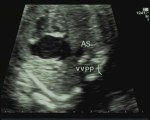

Cuore sinistro ipoplasico

Cuore sinistro ipoplasico e persistenza della vena cava superiore sinistra